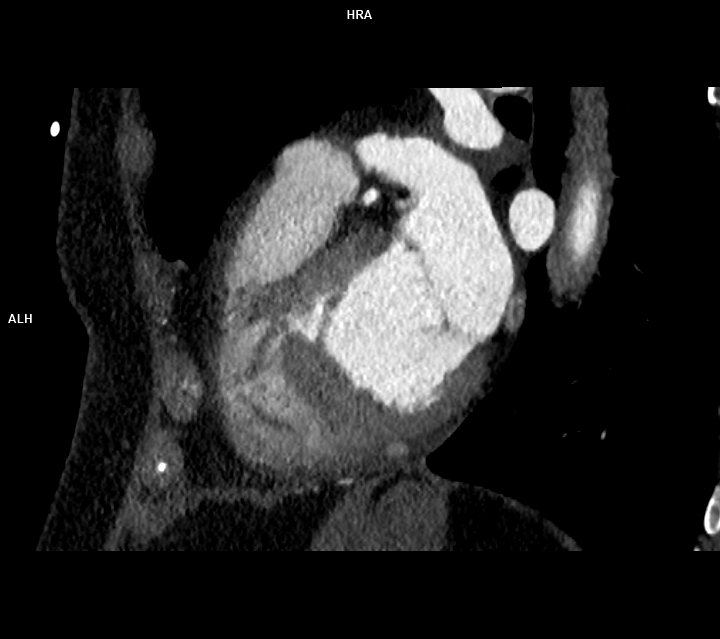

Discuţie caz nr 90: se evidențiază o soluție de continuitate la nivelul septului interventricular în treimea medie cu diametrul de 0.2 cm ce este restricționat de trabecule ventriculare drepte și de crista supraventricularis. La acest pacient a fost descoperire întâmplătoare, indicația de efectuare a examinării cardioCT era boală coronariana cronică.

DE LUAT ACASĂ!!! Un defect de sept interventricular mic, restricționat de trabeculele VSD, este un tip de VSD în care defectul este blocat parțial sau complet de fibrele musculare și crestele din ventriculul drept, limitând fluxul de sânge prin DSV și reducând potențial severitatea shuntului. Pentru evidențierea suntului este utilă completarea cu examinare cardio-RM pentru calcularea raportului Qp : Qs prin hărți de velocitate.